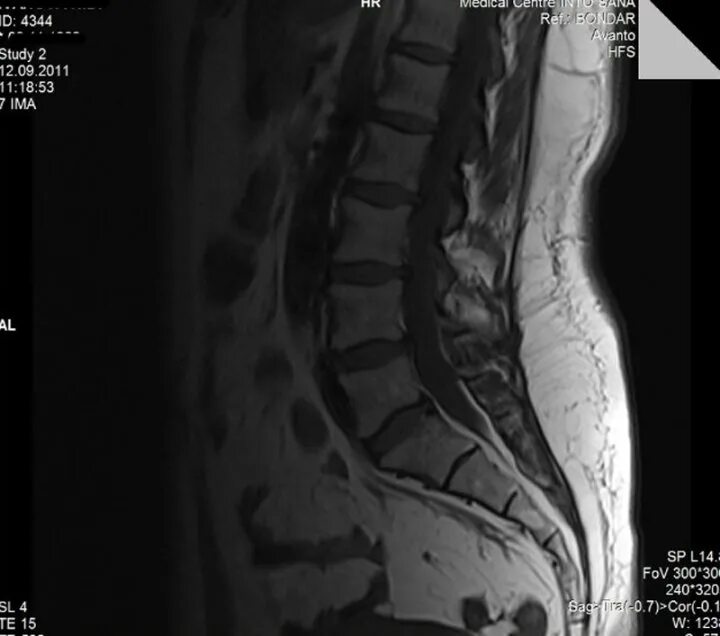

Как лечить спондилоартроз пояснично крестцового отдела позвоночника